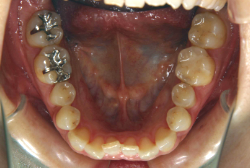

「左奥歯でものが噛めない」という主訴で来院したケースです。診断の結果、基本的には「叢生」という隙間が足りないと言うことが原因の凸凹症例でしたが、左下の乳歯が高校生になってもまだ残存している状態で、そのせいで噛み合わせが極端に悪くなっていました。

検査の結果、乳歯の下には後継ぎの永久歯が先天的に欠如していました。配列の凸凹が厳しく非抜歯で矯正することは難しく、仮に無理をして非抜歯治療をしても後々「後戻り」が懸念されることから、このような症例の場合は通常、上下顎左右第一小臼歯を抜歯させていただくのですが、左下は乳歯を抜歯して、第一小臼歯は残すことにしました。これで結果として、小臼歯部を上下左右で一つずつ減らしたのと同じ状況になります。治療後は歯並びが綺麗になっただけでなく、噛み合わせ的にも正しい状態が確立しています。

このように、先天的に永久歯が足りないという症例は最近増えています。親知らずはなくても特に問題になりませんが、その他の歯が足りないと言うのは審美的にも機能的にも重大な障害となります。しかし、矯正治療を正しく行えば、結果として歯がすべてあった場合と全く同じ仕上げにすることも可能です。